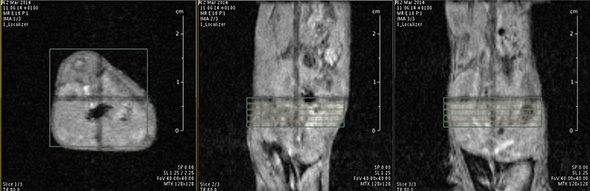

MRI is based on NMR Spectroscopy, which is the best language to talk to nature. We know how it is important to exploit different field strengths in order to extract maximum information from the system that we are investigating.

I think that also the low-field, let’s say the low/intermediate field to work at the 1 Tesla for instance as in the case of this beautiful Icon system, this gave us unique possibilities. Anytime we use a gadolinium-based agent or more in general a paramagnetic basic agent the best field is the 1 Tesla.

So, we can show that there is a real advantage of working at 1 Tesla in comparison to for instance 7 or 9 Tesla when one is using a relaxation enhancer to target a specific epitope in the region of interest.

The possibility to use complementary imaging modality was our task in the last 10 or so years. And this changed quite drastically the structure of our group, because we have to get users quickly used to the basic principles in order to have efficient imaging reporter for the other imaging modalities.